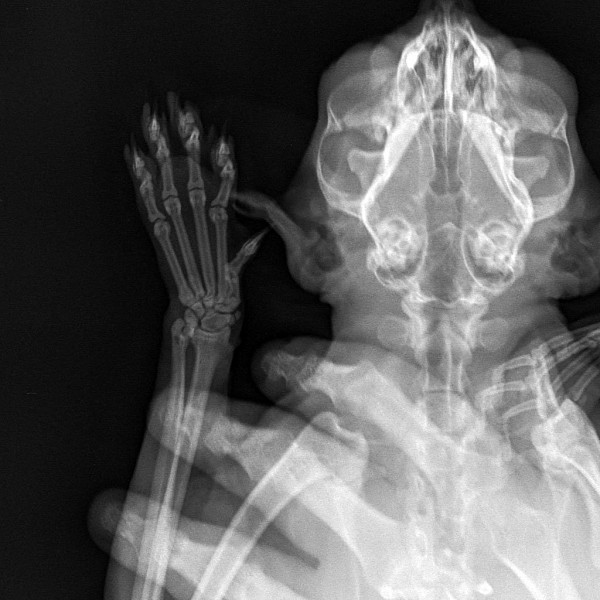

Сделали 3 рентгеновских снимка:

http://www.imageup.ru/img14/3262899/2019-01-18-pestrushka-03.jpg

На снимке головного мозга кошки врач предположительно нашёл небольшие тёмные пятна справа (???), и сказал, что это расширенные сосуды по типу варикоза и они давят на мозг, в результате чего животное бьётся в судорогах. Но это неточно и нужны консультация ветеринара-невропатолога и МРТ головного мозга кошки.